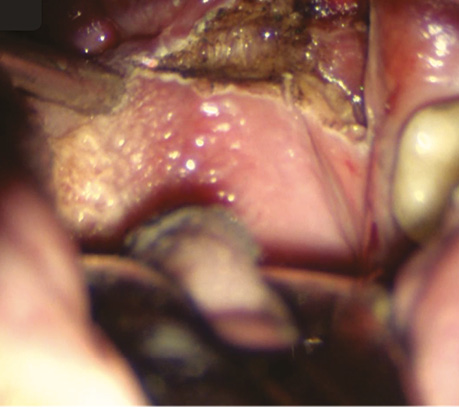

Рис. 5. Виділено та кліповано a. dorsalis linguae

Рис. 6. Вид операційної рани після трансоральної CO₂-лазерної резекції бічної стінки ротової частини глотки та кореня язика